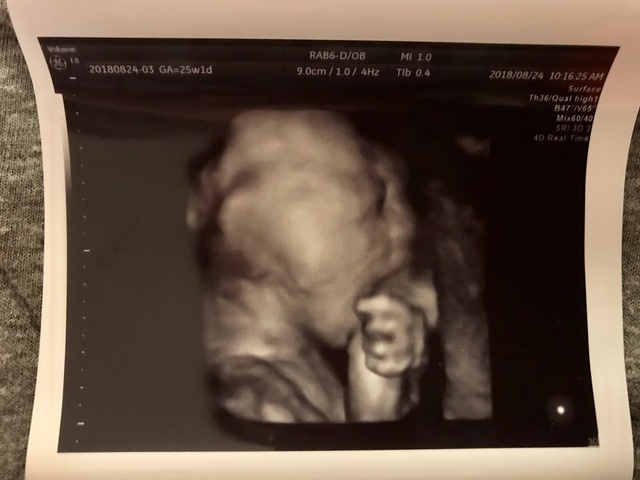

25週1日(25w1d・男の子)|plzLM_ さん(25歳)

エコー写真撮影時のエピソード:

妊娠するとトイレが近くなりますが、エコーの際はおしっこがある程度溜まっていた方が赤ちゃんがきれいに映りやすいとお医者さんが言っていたので、検診前は行かないようにしていました!

息子は常に手や足で顔を隠していましたが、それが鮮明に映っていました!